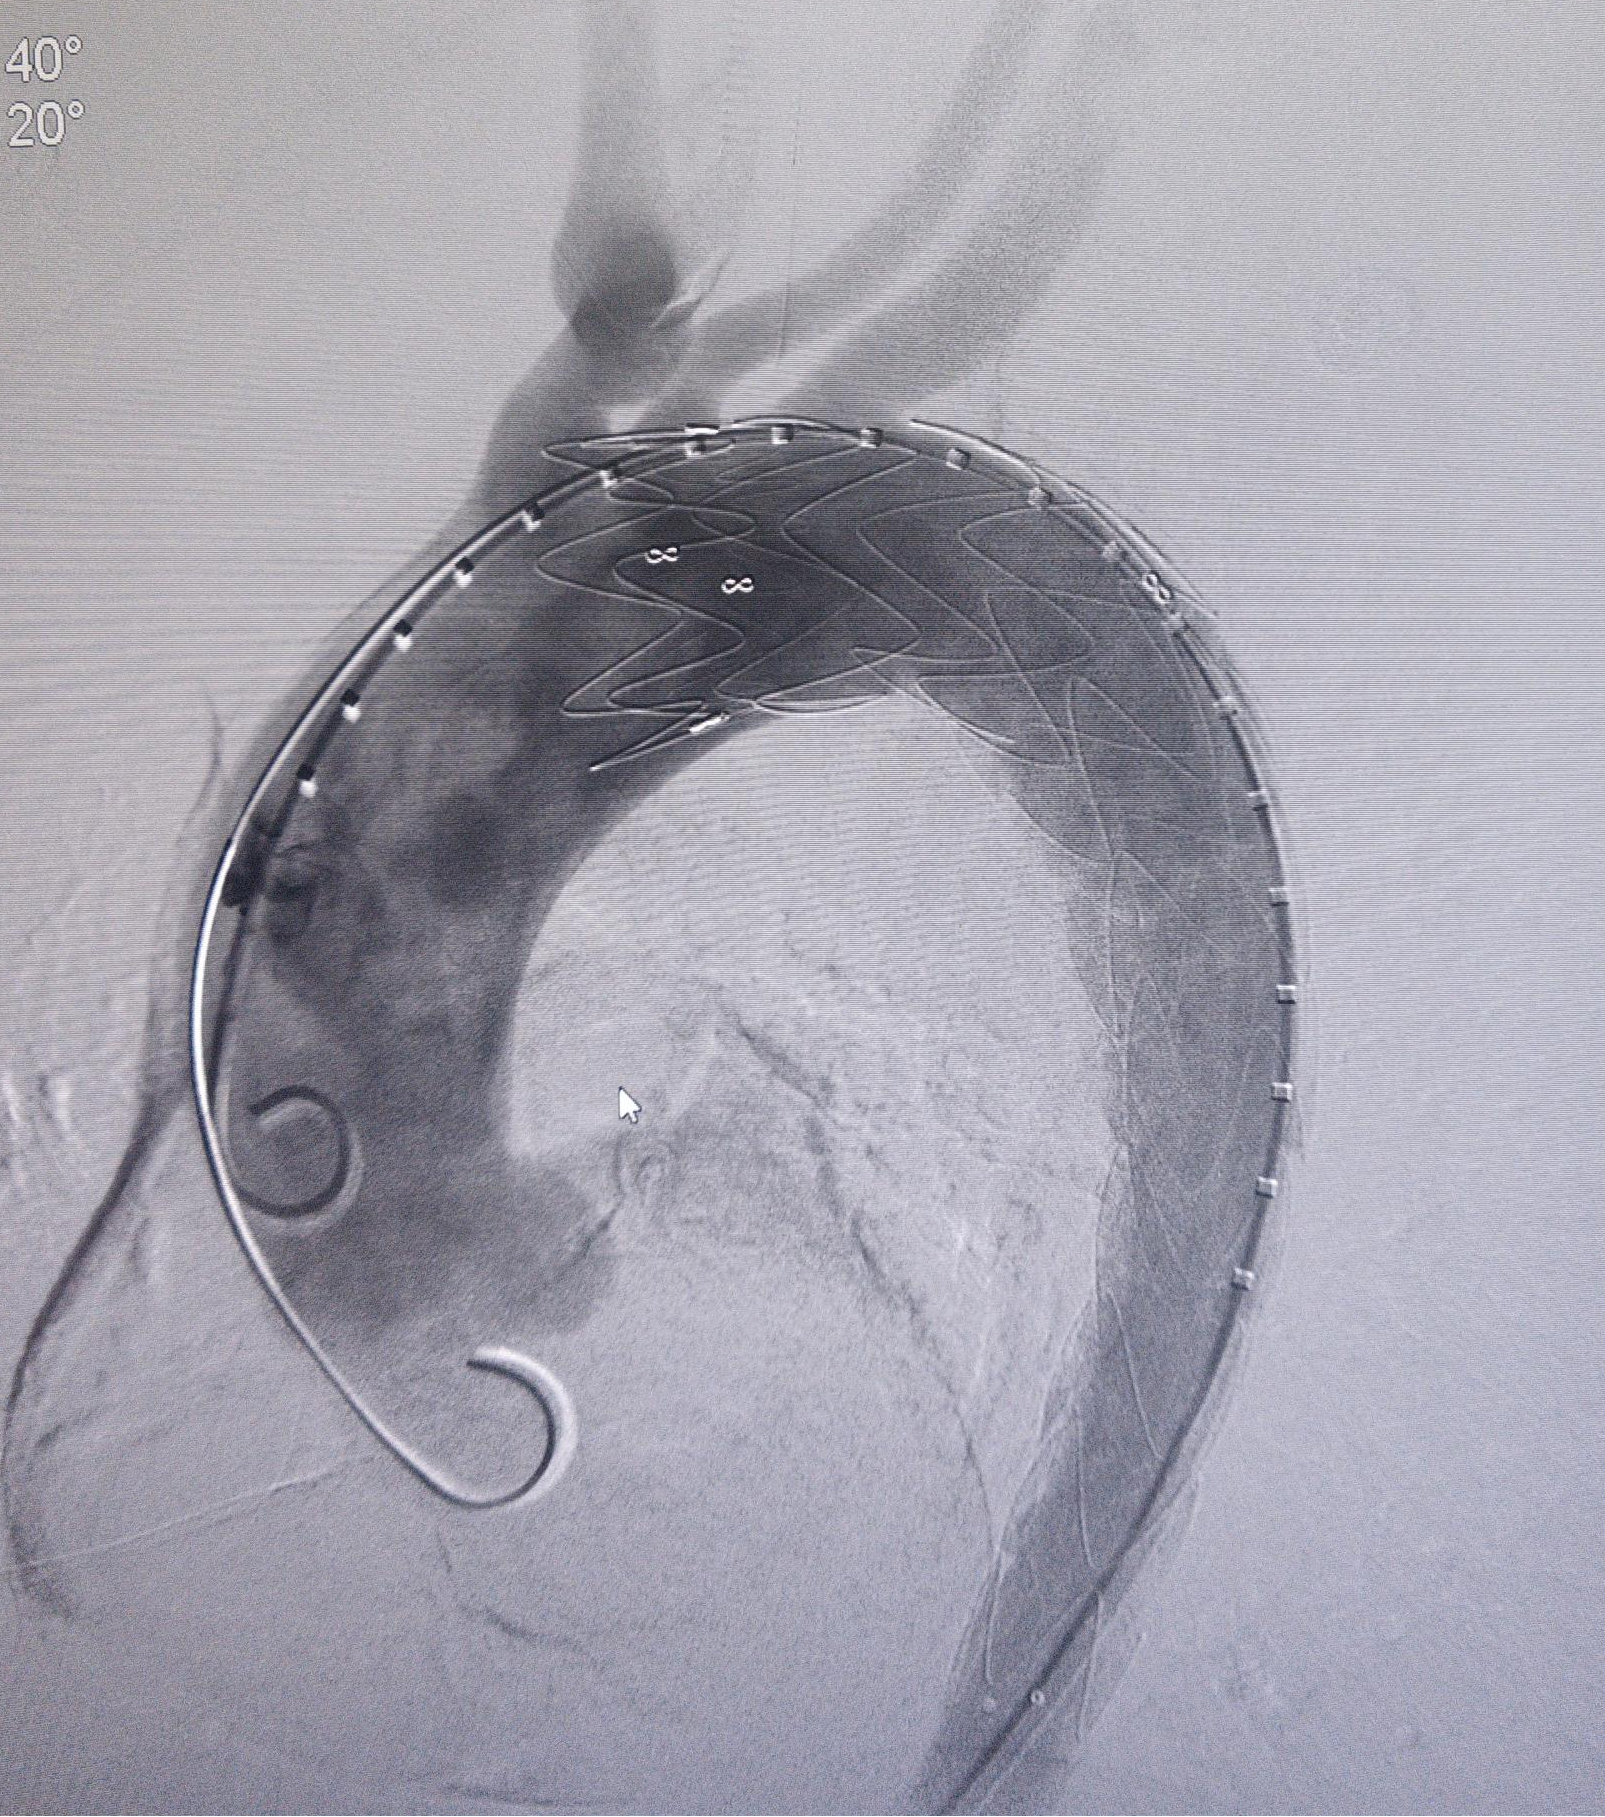

手术期间,术中造影清晰显示出主动脉夹层破口。团队按照术前规划对覆膜支架完成体外开窗操作,随后精准锚定并释放支架。术后造影验证显示,患者夹层破口封堵良好,左锁骨下动脉等分支血管血供正常,手术圆满成功。术后患者恢复顺利,生命体征平稳,仅1天便能下床活动。

依据术前规划对覆膜支架进行体外开窗

精准锚定并释放支架,术后造影,破口封堵良好,分支血管血供良好